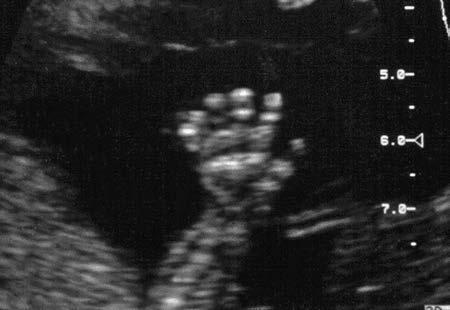

electronic instrument by the interaction of ultrasound with the object. Ultrasound provides a noninvasive way of looking inside the human body (Figure 1-1 ) to image otherwise hidden anatomy. Anatomic imaging with ultrasound is accomplished with a pulse-echo technique . Pulses of ultrasound generated by a transducer are sent into the patient ( Figure 1-2 ), where they produce echoes at organ boundaries and within tissues. These echoes return to the transducer,

where they are detected and presented on the display of a sonographic instrument. The transducer ( Figure 1-3 ) generates the ultrasound pulses and receives the returning echoes. Sonography requires knowledge of the location of origin of each echo and its strength as it returns from the patient. The ultrasound instrument (Figure 1-4 ) processes the echoes and presents them as visible dots, which form the anatomic image on the display. The brightness

1-1 Ultrasound provides a window into the human body, allowing us to see what would otherwise be hidden from view (A-B). Images shown are as follows: C, abdominal; D, cardiac; E, obstetric, and F, vascular.